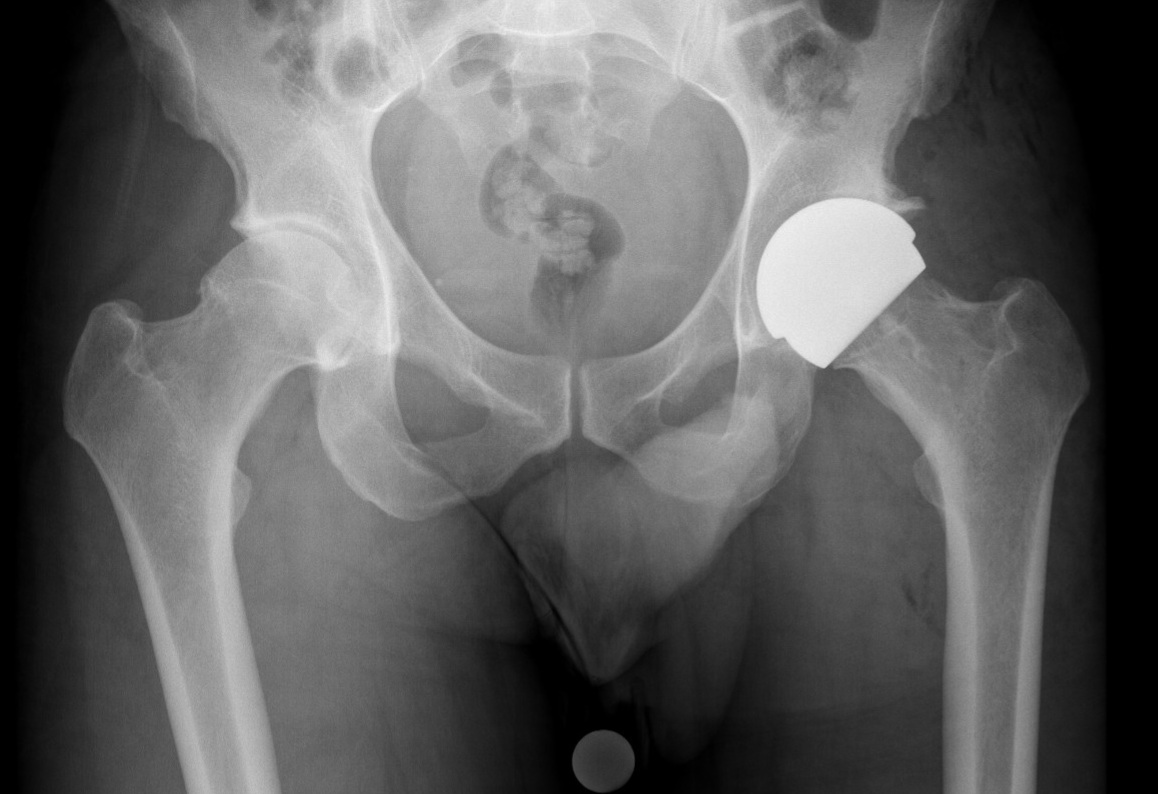

Hip Resurfacing

Hip resurfacing preserves more of the patient’s natural bone by capping the femoral head with a ceramic surface rather than removing it entirely. It's often considered for younger, active patients with strong bone quality.